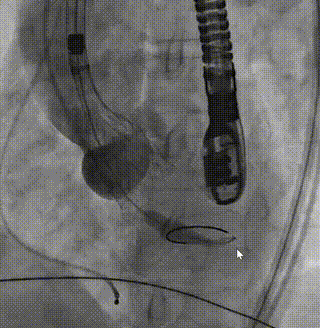

部分释放

造影评估深度1

造影评估深度2